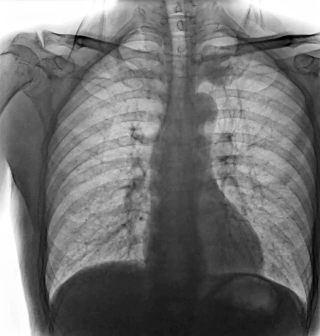

靜態(tài)DR受限于二維成像,在拍攝隱匿性病灶時,由于組織重疊病灶難辨,耗費時間更長且易漏診、誤診。而動態(tài)DR則具備實時動態(tài)成像功能,可通過實時連續(xù)成像,對于重疊部位病灶或者易被遮擋的病灶進行多角度動態(tài)觀察,快速實現(xiàn)動靜態(tài)轉(zhuǎn)換點片。

因此,動態(tài)DR在精準診斷方面具有顯著優(yōu)勢。首先,有效減少誤診漏診,如胃腸道造影中,可實時觀察鋇劑的流動和充盈過程,精準發(fā)現(xiàn)病灶部位,避免靜態(tài)DR攝片時機不當?shù)膯栴}。其次,提升復雜檢查能力,如食管吞咽功能評估、四肢關(guān)節(jié)動態(tài)活動度評估等,動態(tài)DR都能提供關(guān)鍵性的診斷依據(jù)。同時,還可以優(yōu)化流程效率,醫(yī)生在擺位時能通過動態(tài)影像快速找到最佳投照角度,減少重復拍片,降低患者輻射劑量。